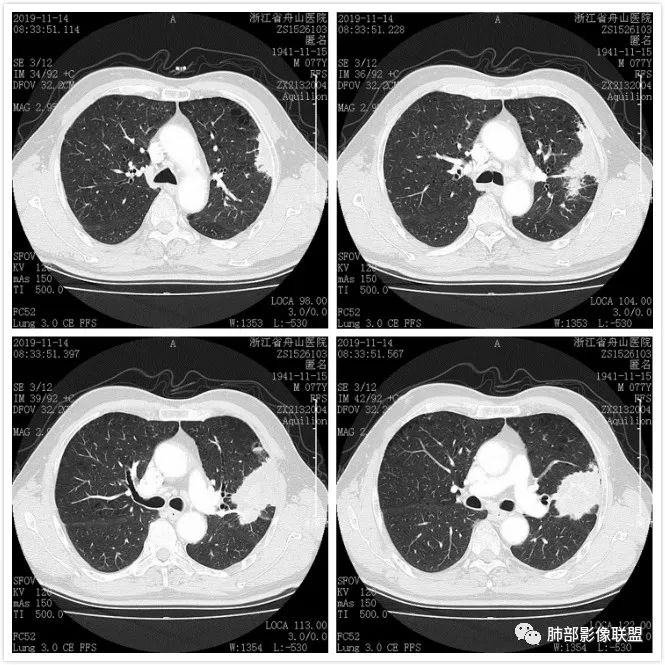

真假支气管爬行征—肺腺癌1例CT影像讨论

影像资料

病例讨论

毛勤香:左肺上叶病灶,外朝内生长,分叶状,气管闭塞,血管有破坏,增强明显强化不均匀,较多低密度区,考虑恶性,肉瘤样癌?腺癌或腺鳞癌?左肺下叶多发小结节,转移? 医学百科网 | YxBaike.Com

小强:牵拉,收缩力,考虑恶性,腺癌? 医学百科网 | YxBaike.Com

光明:肿块和实变,密度低,支气管阻塞,血管破坏,考虑粘液腺癌? 医学百科网 | YxBaike.Com

王秀仙:左肺上叶肿块,支气管进入阻塞,边缘膨隆,斜裂牵拉凹陷,与胸膜宽基底相连,强化较低,内可见强化血管,部分血管侵蚀模糊,下叶可见多发结节,考虑粘液腺癌

林漠:考虑肺癌,边缘膨胀,支气管鼠尾状截断,斜裂牵拉。考虑粘液腺癌 医学百科网 | YxBaike.Com

binby:感觉外往内长。累及多支支气管。包绕一部分不是截断,有鼠尾感。压迫性狭窄 医学百科网 | YxBaike.Com

雪狐7305:恶性,病理倾向鳞癌:老年男性,肺气肿背景,左上叶肿块,膨隆,分叶,强化,血管有破坏,舌支鼠尾样闭塞,考虑鳞癌可能性大 医学百科网 | YxBaike.Com

这个病例似乎是外头大内头小,由外围往内蔓延,和我们常讲的结核的支气管爬行征有类似地方。 医学百科网 | YxBaike.Com

那么它到底是不是结核肉芽肿呢?我们先来复习下支气管树爬行征的影像应该同时符合以下四条:1.近端支气管通畅,2.病侧肺容积正常,3.外周朝内侧生长,4.外宽内窄逐渐“爬行”向肺门。 医学百科网 | YxBaike.Com

那么我们对照来看到底符不符合呢?首先这个病例近段支气管是鼠尾样狭窄的,所以第一条就不能满足,况且此病灶还具有边缘膨隆,周边有细短毛刺,内不均匀强化,内血管破坏等恶性特点,所以此征不等同于肉芽肿型的爬行征,切不可以误用概念征象。

图一:可见支气管狭窄截断,图二,肿块内血管破坏,图三边缘膨隆毛刺